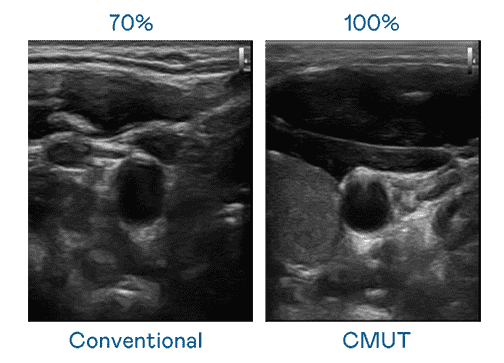

CMUT 技术是一种用电容式微机电元件来产生超音波讯号的技术。。与传统 PZT 压电式技术相比,,CMUT 频宽增加 30%,,更宽频的超音波讯号让影像解析度大幅提升,,,是实现高影像品质医疗超音波扫描、、、促进精准医疗发展的关键技术。。。。

大频宽带来超清晰影像

超音波影像的解析度高低,,,首先取决于探头能发出的讯号频宽。。云顶国际8588yd CMUT 可提供高清晰的超音波讯号,,,提供高频宽、、、高灵敏度、、影像纹理细节更高的超音波影像,,,,协助医护人员缩短影像判读时间及利用精准的医疗影像进行诊断。。